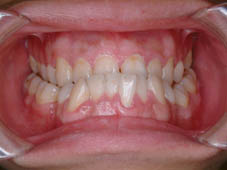

案例一:手術前